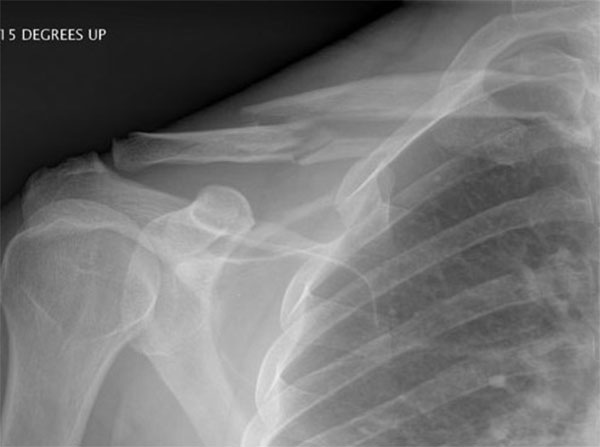

Move the slider to compare before surgery and 6 weeks after surgery

This lady is 65 years old and fractured her clavicle 28 years previously in a motor vehicle accident. At that time she was told that nothing could be done for her. It never really healed and as a result she had ongoing pain in her scapula, shoulder and clavicle. I managed to fix her fracture with a plate and screws and kept her in a sling longer than I normally would and reviewed her for a longer period of time than normal but at her final visit eleven months after her surgery she was delighted with the result as she had no pain, a full range of motion, the fracture was solidly healed and she was doing everything she wanted to do.

Malunion fracture before surgery

Malunion fracture after surgery

Move the slider to compare before surgery and 11 months after surgery